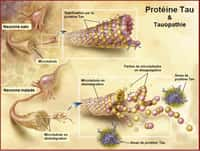

La maladie d'Alzheimermaladie d'Alzheimer est une maladie neurodégénérativemaladie neurodégénérative qui survient autour de 65 ans. Elle touche les fonctions cognitives et se répercute sur le comportement social des patients. À travers une approche interdisciplinaire, différents spécialistes font le point sur l'état actuel des recherches susceptibles d'apporter une meilleure compréhension des difficultés cognitives liées à l'âge et à Alzheimer.

Après avoir explicité les concepts de ressource adaptative et de mémoire chez l'adulte vieillissant, les auteurs livrent une analyse approfondie des mécanismes du vieillissement cérébral et de la maladie d'Alzheimer. Sont aussi passés en revue les différents facteurs de risquefacteurs de risque, les possibilités de préventionprévention, et les ouvertures thérapeutiques. Le but étant de faire apparaître la compatibilitécompatibilité et la complémentarité des approches psycho-sociales et biologiques.